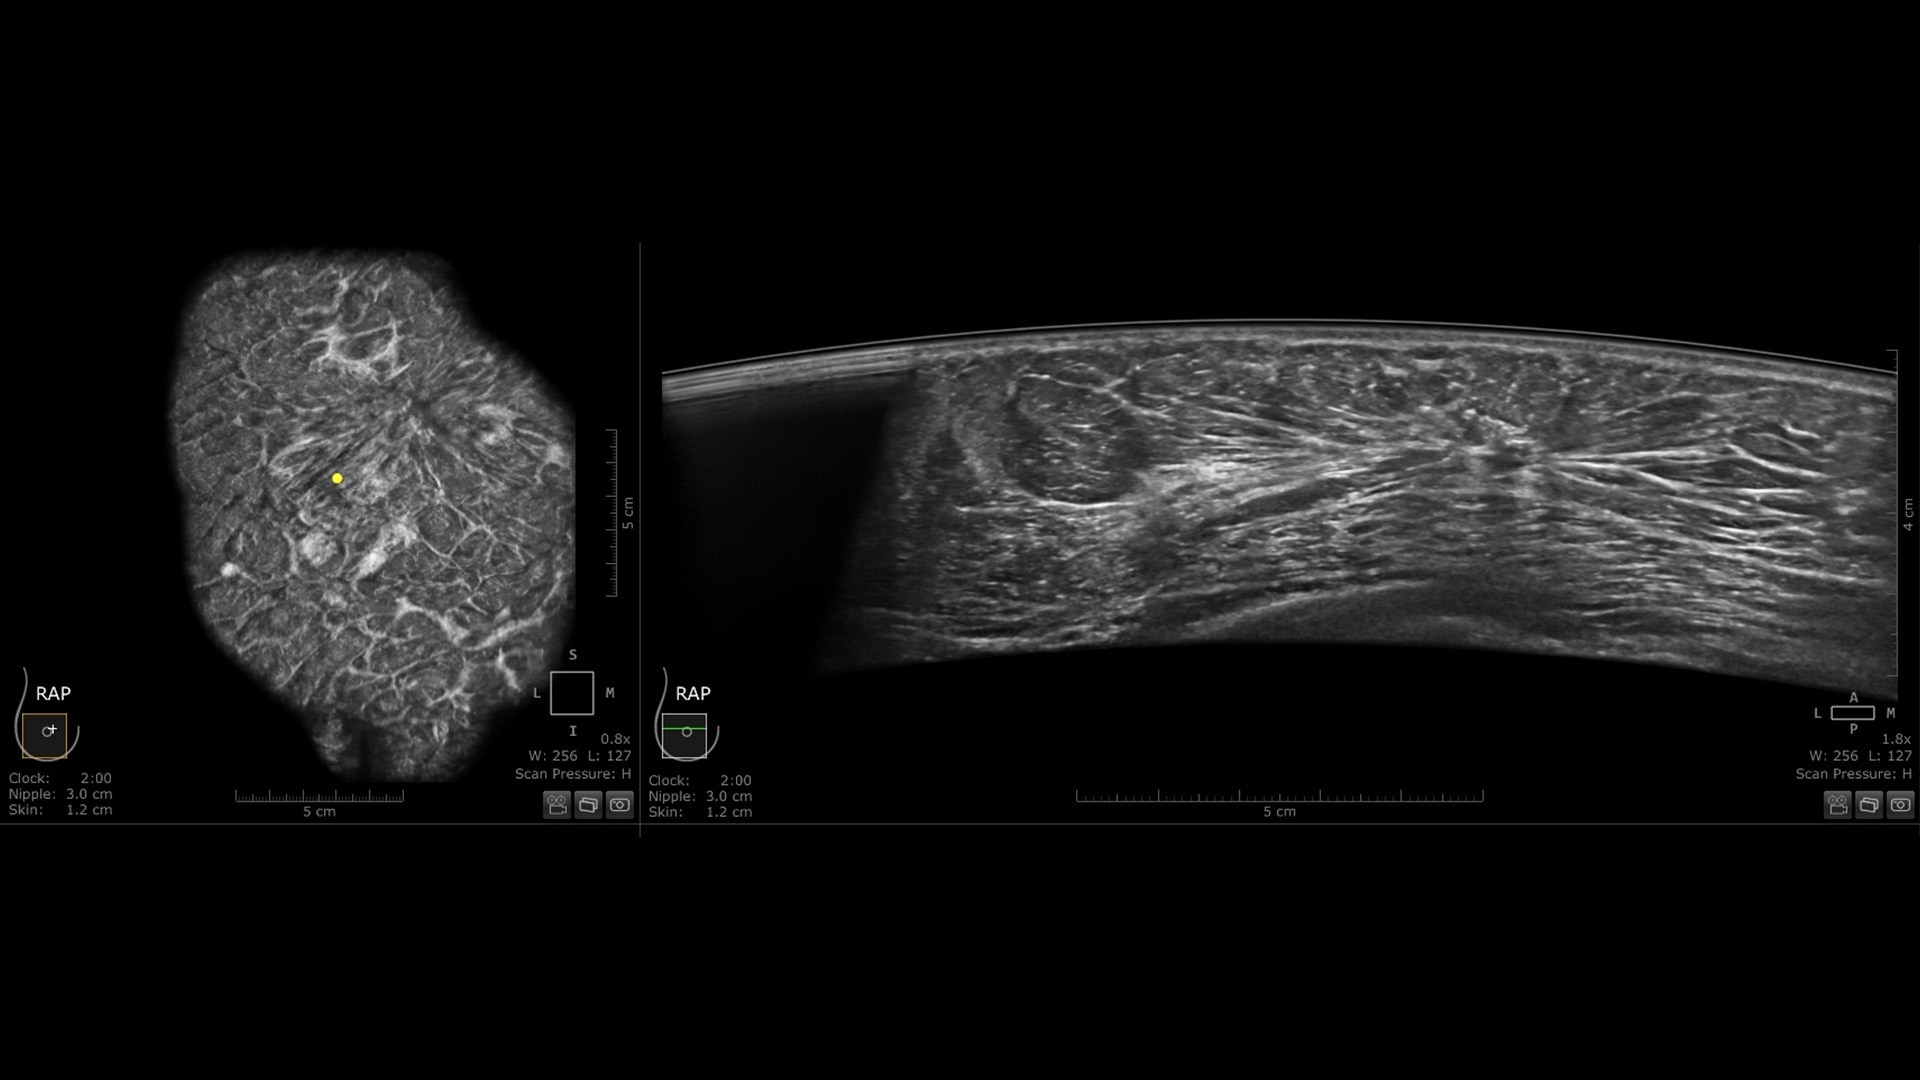

Productivity powered by AI

Boost clinical confidence and efficiency with AI-driven scanning and reading